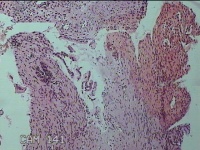

宫颈息肉

性别

女

年龄

29岁

临床诊断

一般病史

标本名称

大体所见

灰白暗红色不规则碎组织1.2x0.8x0.3cm一堆,表面光滑。

良性病变。